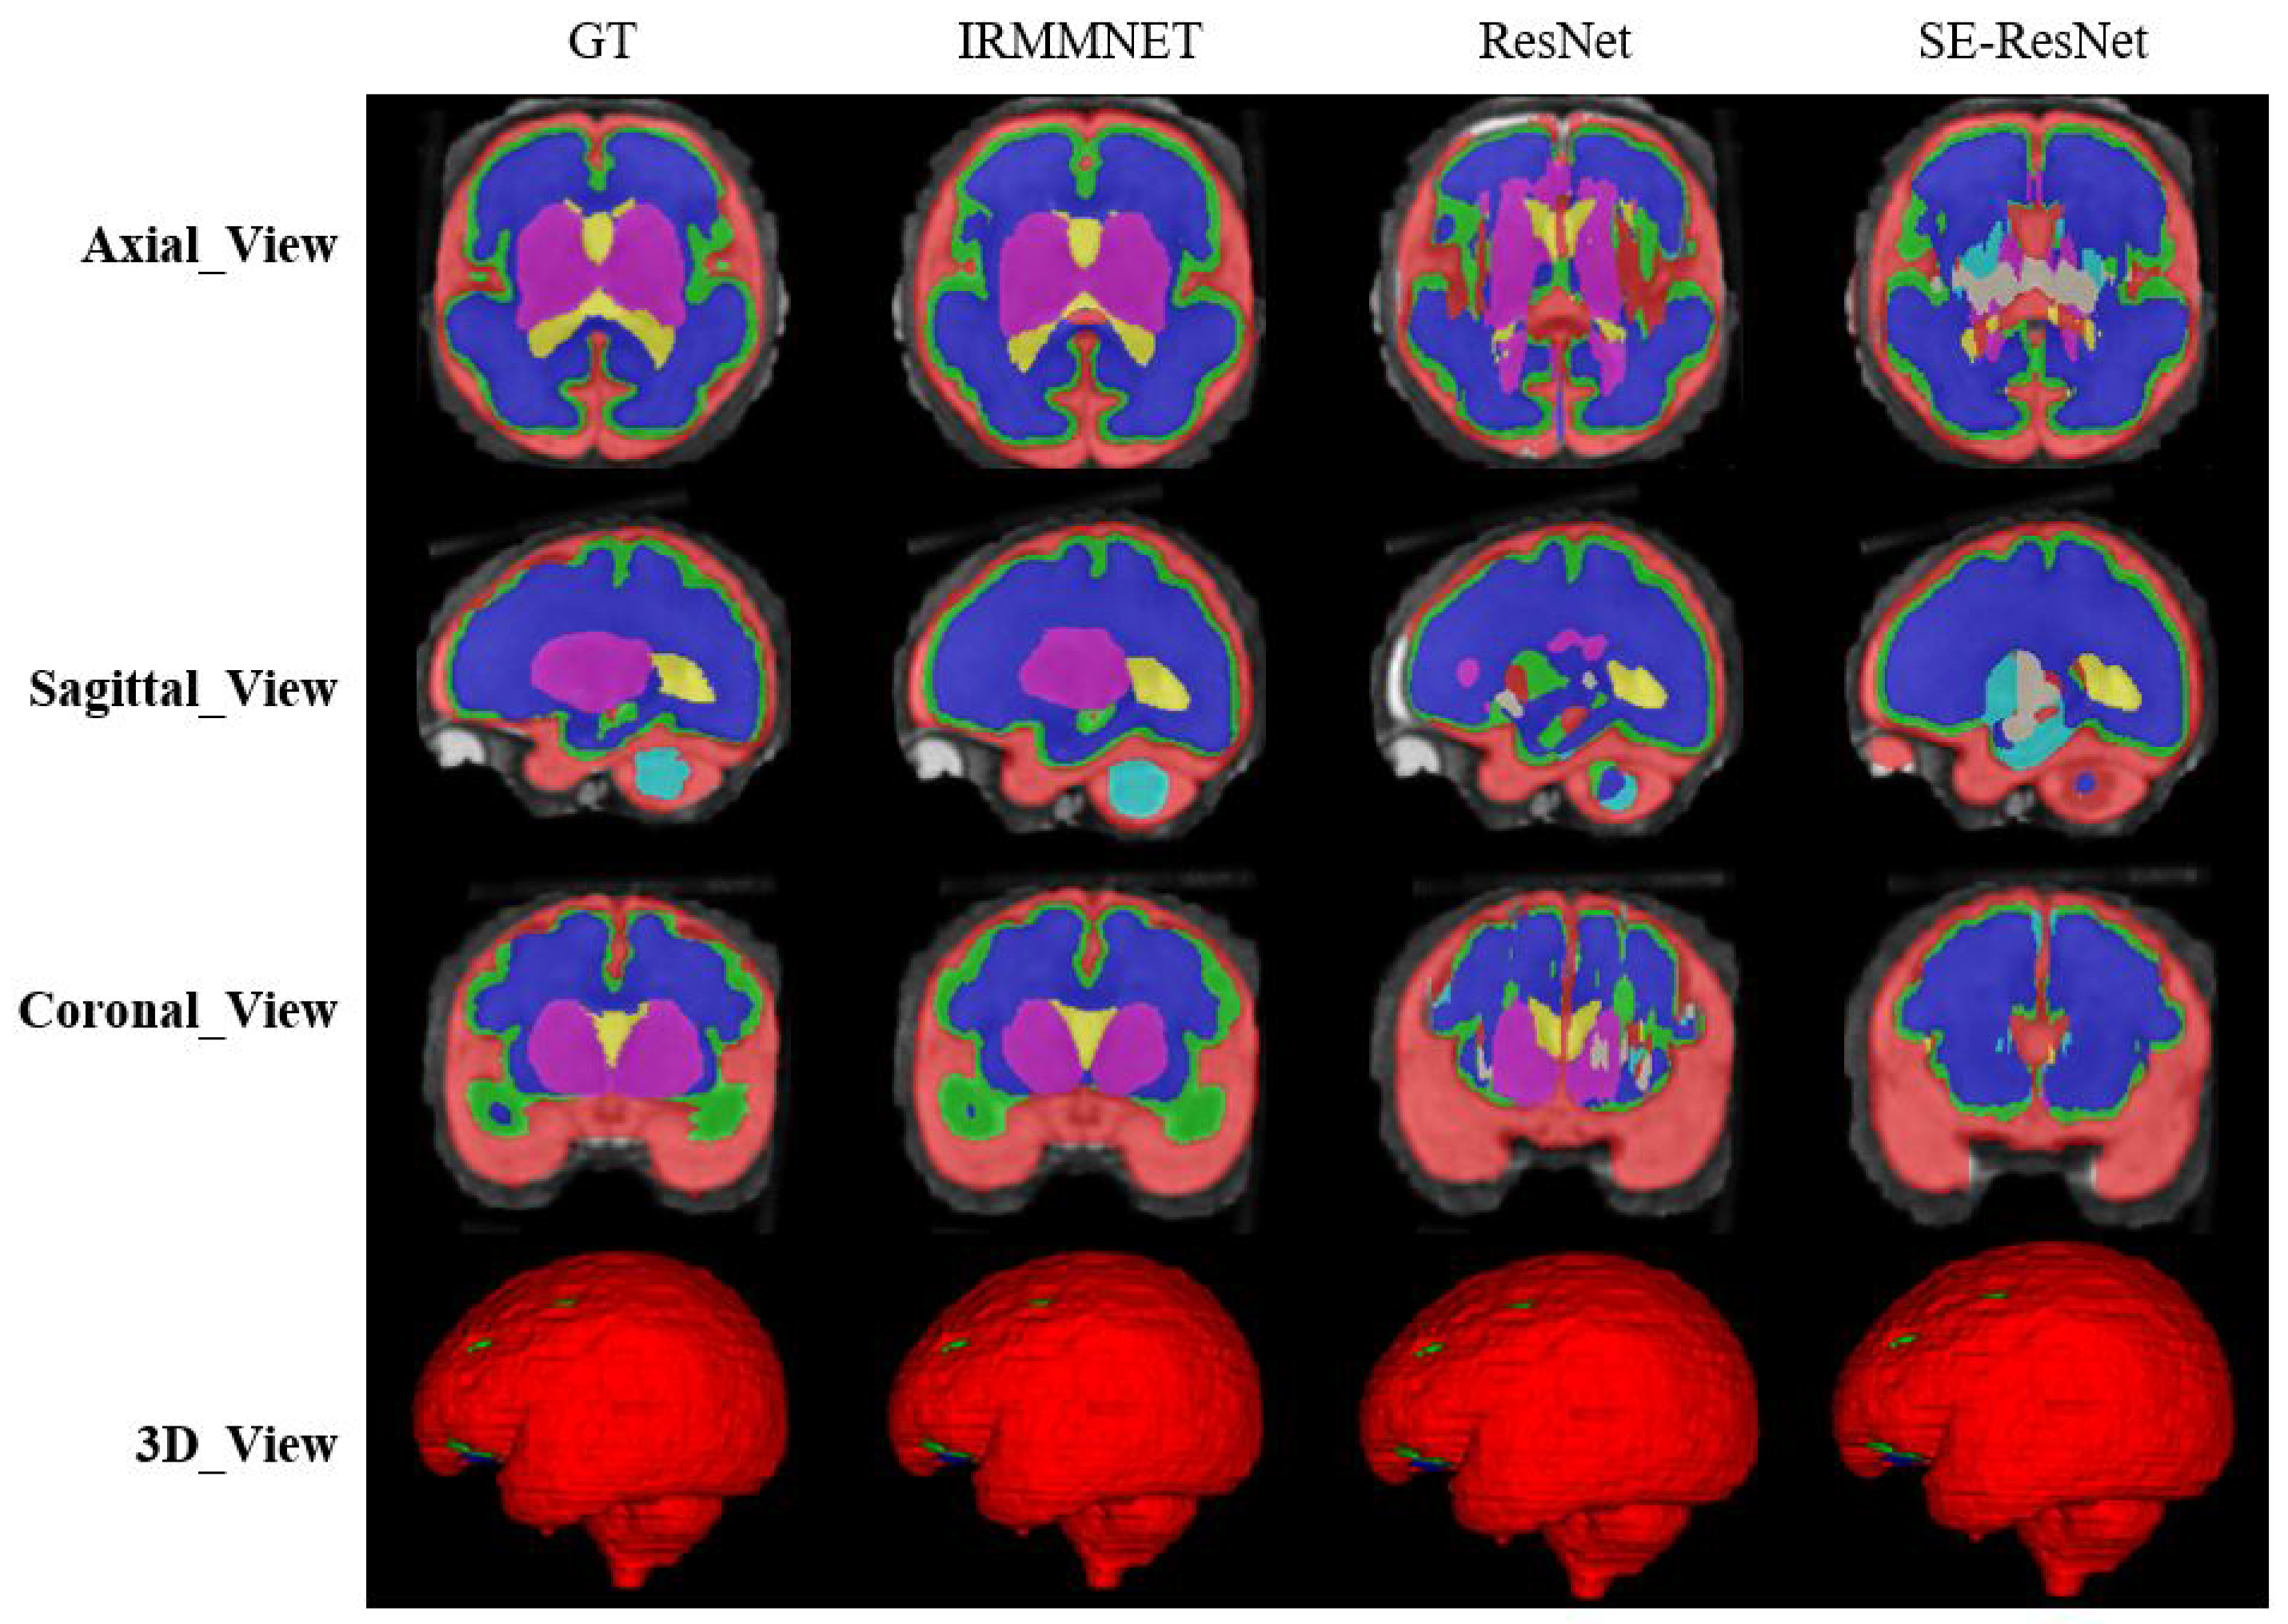

Figure 9 shows the proposed IRMMNET model’s segmentation maps for the axial, sagittal, and coronal planes. In addition, 2D and 3D volumetric views of the segmentation images are shown in Figure 9 for the axial, sagittal, and coronal planes. It can be visibly noticed that the coronal-view model generated accurate segmentation masks, in which the predictions for the deeper and smaller classes were close to the GT. It should be noted that the proposed model was initially tried on the 2D axial slices, but the predicted segmented images yielded a bad prediction for the deep classes. Therefore, the proposed segmentation model was applied to the three views’ 2D slices (axial, sagittal, and coronal) for fetal brain segmentation. Among the predicted segmentation results for the fetal brain, the 2D coronal view produced the best results.

Figure 9. The segmentation maps of the proposed model with different views.

Entropy 24 01708 g009